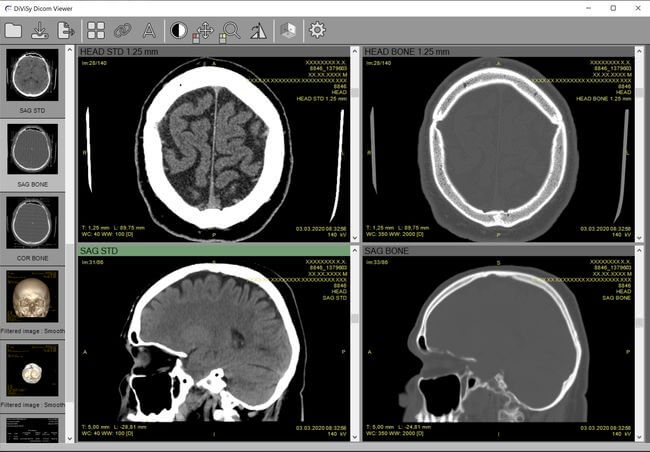

DICOM-вьюер — это специализированное программное обеспечение, предназначенное для отображения и анализа медицинских изображений, таких как рентген, КТ, МРТ и ультразвуковые исследования https://dicom-viewer.online. Он позволяет врачам визуализировать изображения, проводить измерения, контурировать области интереса и анализировать данные для более точной диагностики. Онлайн DICOM-вьюер, в отличие от традиционных программ, доступен прямо в браузере, что упрощает доступ и совместное использование информации.

Онлайн DICOM-вьюеры предлагают широкий набор инструментов для анализа изображений. Пользователи могут проводить измерения, такие как размеры опухолей или длина сосудов, а также контурировать области интереса для более детального изучения. Эти функции помогают врачам более точно оценивать состояние пациента и принимать обоснованные решения о лечении.